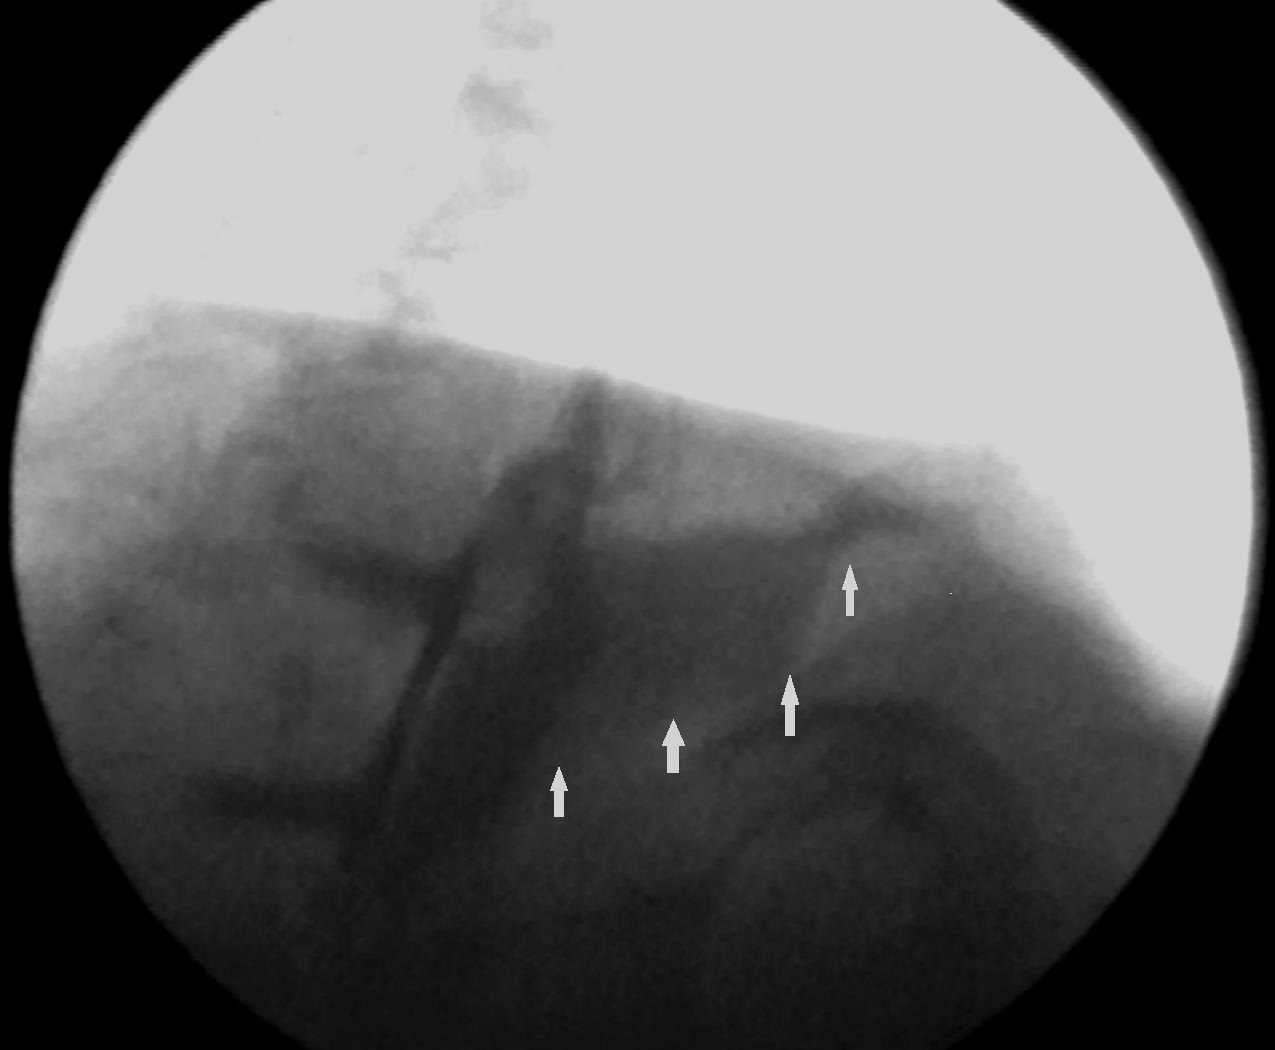

Esophagography. Arrows demonstrate a small posterior pseudodiverticulum of the esophagus adjacent to the metallic plate and screws (Courtesy Dr. V. Penopoulos)